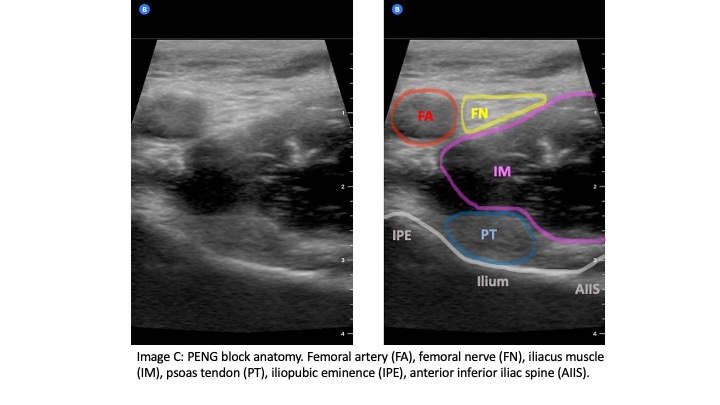

The curvilinear probe is used at an oblique angle parallel to the IL with probe marker to the patient's right side. The linear probe may be used in patients who are thin for better image resolution. Initially, the probe should be positioned inferior to the IL to identify the femoral head (Image B). Then the probe can be moved cranially until the anterior inferior iliac spine (AIIS) and iliopubic eminence (IPE) of the ilium are visualized (Image C). The femoral artery, femoral nerve, iliacus muscle and psoas tendon should be identified. The femoral nerve generally lies right above the psoas tendon on top of the iliacus muscle and is just lateral to the femoral artery. The target is the subfascial plane located underneath the psoas tendon and above the ilium. A 20G or larger long spinal needle or echogenic nerve block needle is inserted in a lateral-to-medial approach until contact with the ilium is made underneath the psoas tendon (Image D). Hydrodissection of the fascial plane using saline initially helps to visualize the correct location before injecting 20 CCs of long-acting anesthetic, such as ropivacaine or bupivacaine with epinephrine. The block has been shown to be effective with a lower concentration of local anesthetic such as 0.25% bupivacaine with epinephrine.